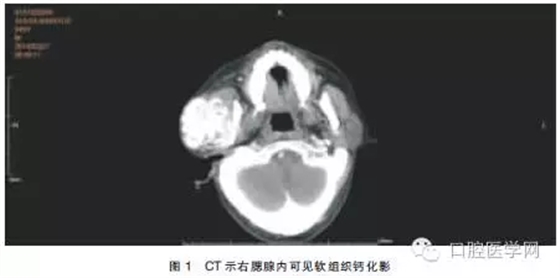

查體:患者面形左右不對稱,右耳前有一約5.0 cm×5.0 cm大小的軟組織隆起,質(zhì)地較硬,與周圍組織界限不清,無活動度,開口度未受影響。血鈣:2.7mmol/L,血磷:2.9mmol/L,肌酐:953μmol/L,尿素氮:5.7mmol/L。使用GE VCT64排螺旋CT進行掃描(球管電流:250mA,掃描電壓:120kV,周期:0.4s/周,層厚:5mm),掃描范圍:顱底至頸根部。結果示:右腮腺區(qū)見團塊狀混雜密度(軟組織內(nèi)伴鈣化)影,邊界欠清,與腮腺組織及血管分界不清,與咬肌及周圍骨結構分界欠清(圖1)。